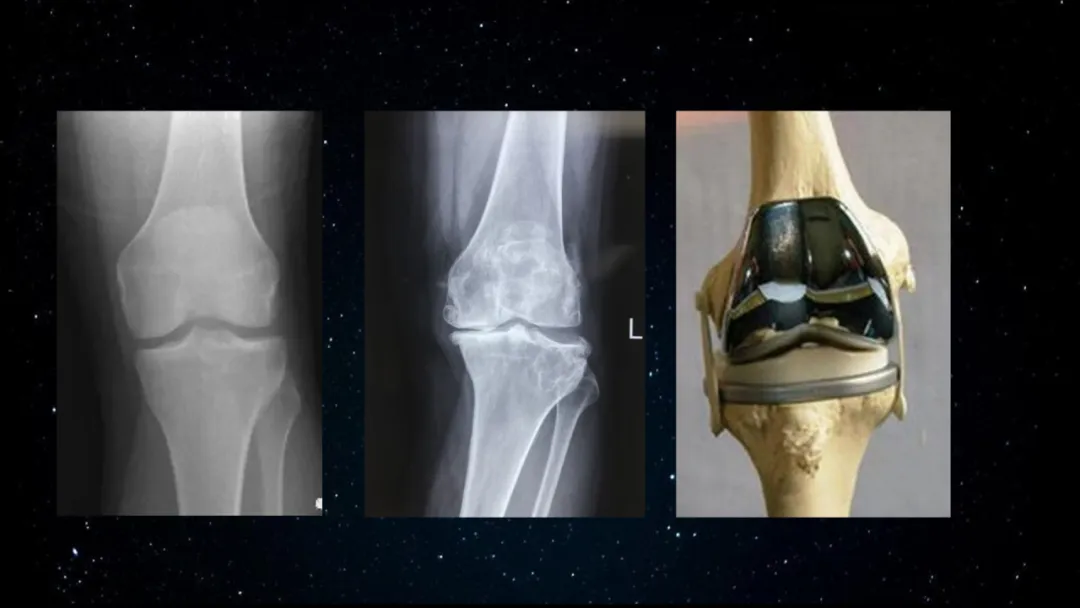

其實我畢業於上海交通大學醫學博士,畢業後一直在上海第六人民醫院骨科工作,我幹了20年的手術醫生。但在我的臨牀工作中,我卻發現在我的病人當中,有些膝關節疼痛,從他開始出現疼痛,到最後出現功能障礙要手術,會有十年的時間,我能做的僅僅是最後一個環節,我把他刀開好了。在這個病的早期和中期,我只能給他止痛藥,甚至封閉針,我沒有辦法去阻礙這個疾病的發展。因此我內心當中一直有個聲音在告訴我,你只是個手術開刀匠,你不是真正的醫生。

我們來看西醫的底層邏輯,建立在解剖學、組織胚胎學、生物化學、分子生物學,這一些基礎學科上的一個醫學體系。當醫生給你問完診後,會給你開很多的化驗單和影像學的檢查單,最後醫生會根據你化驗單的結果和影像的CT磁共振一些檢查結果,給你做一個診斷。通過治療完以後還會再給你做一個血液檢查或者影像學檢查,看你有沒有被治癒了。所以大家會發現,西醫整個邏輯的目標對象是形態人。西醫的邏輯閉環,是通過檢查來分析人體的宏觀,微觀的形態結構是不是正常,從而來進行診斷和療效評判的醫學。